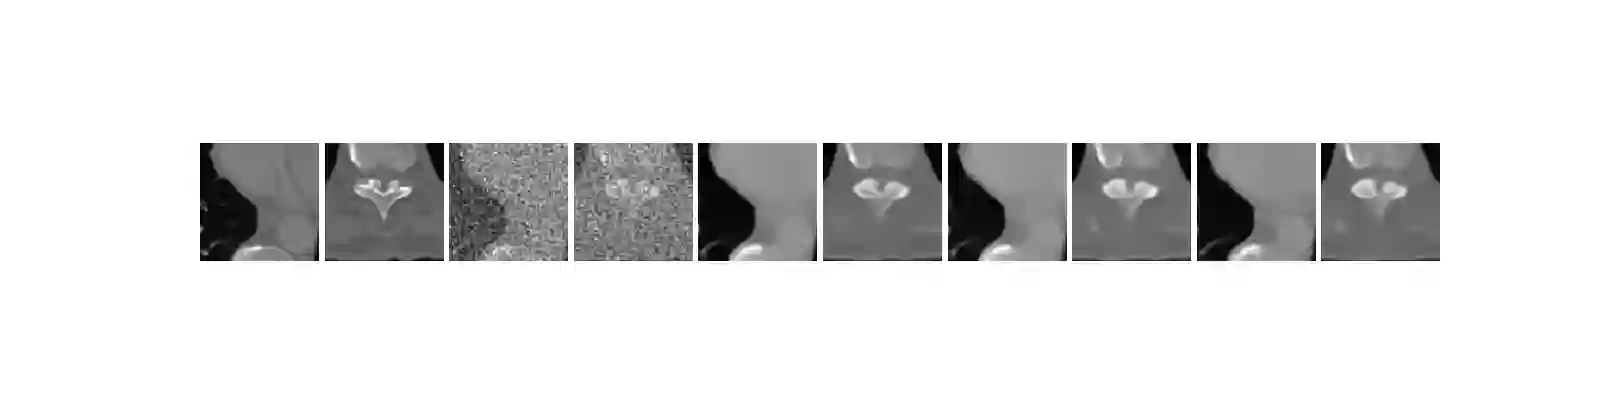

We propose a new type of efficient deep-unrolling networks for solving imaging inverse problems. Conventional deep-unrolling methods require full forward operator and its adjoint across each layer, and hence can be significantly more expensive computationally as compared with other end-to-end methods that are based on post-processing of model-based reconstructions, especially for 3D image reconstruction tasks. We develop a stochastic (ordered-subsets) variant of the classical learned primal-dual (LPD), which is a state-of-the-art unrolling network for tomographic image reconstruction. The proposed learned stochastic primal-dual (LSPD) network only uses subsets of the forward and adjoint operators and offers considerable computational efficiency. We provide theoretical analysis of a special case of our LSPD framework, suggesting that it has the potential to achieve image reconstruction quality competitive with the full-batch LPD while requiring only a fraction of the computation. The numerical results for two different X-ray computed tomography (CT) imaging tasks (namely, low-dose and sparse-view CT) corroborate this theoretical finding, demonstrating the promise of LSPD networks for large-scale imaging problems.